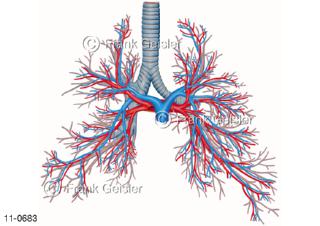

11-0683 Atemtrakt Luftröhre Trachea, Bronchialbaum mit Bronchien und Lungengefäße